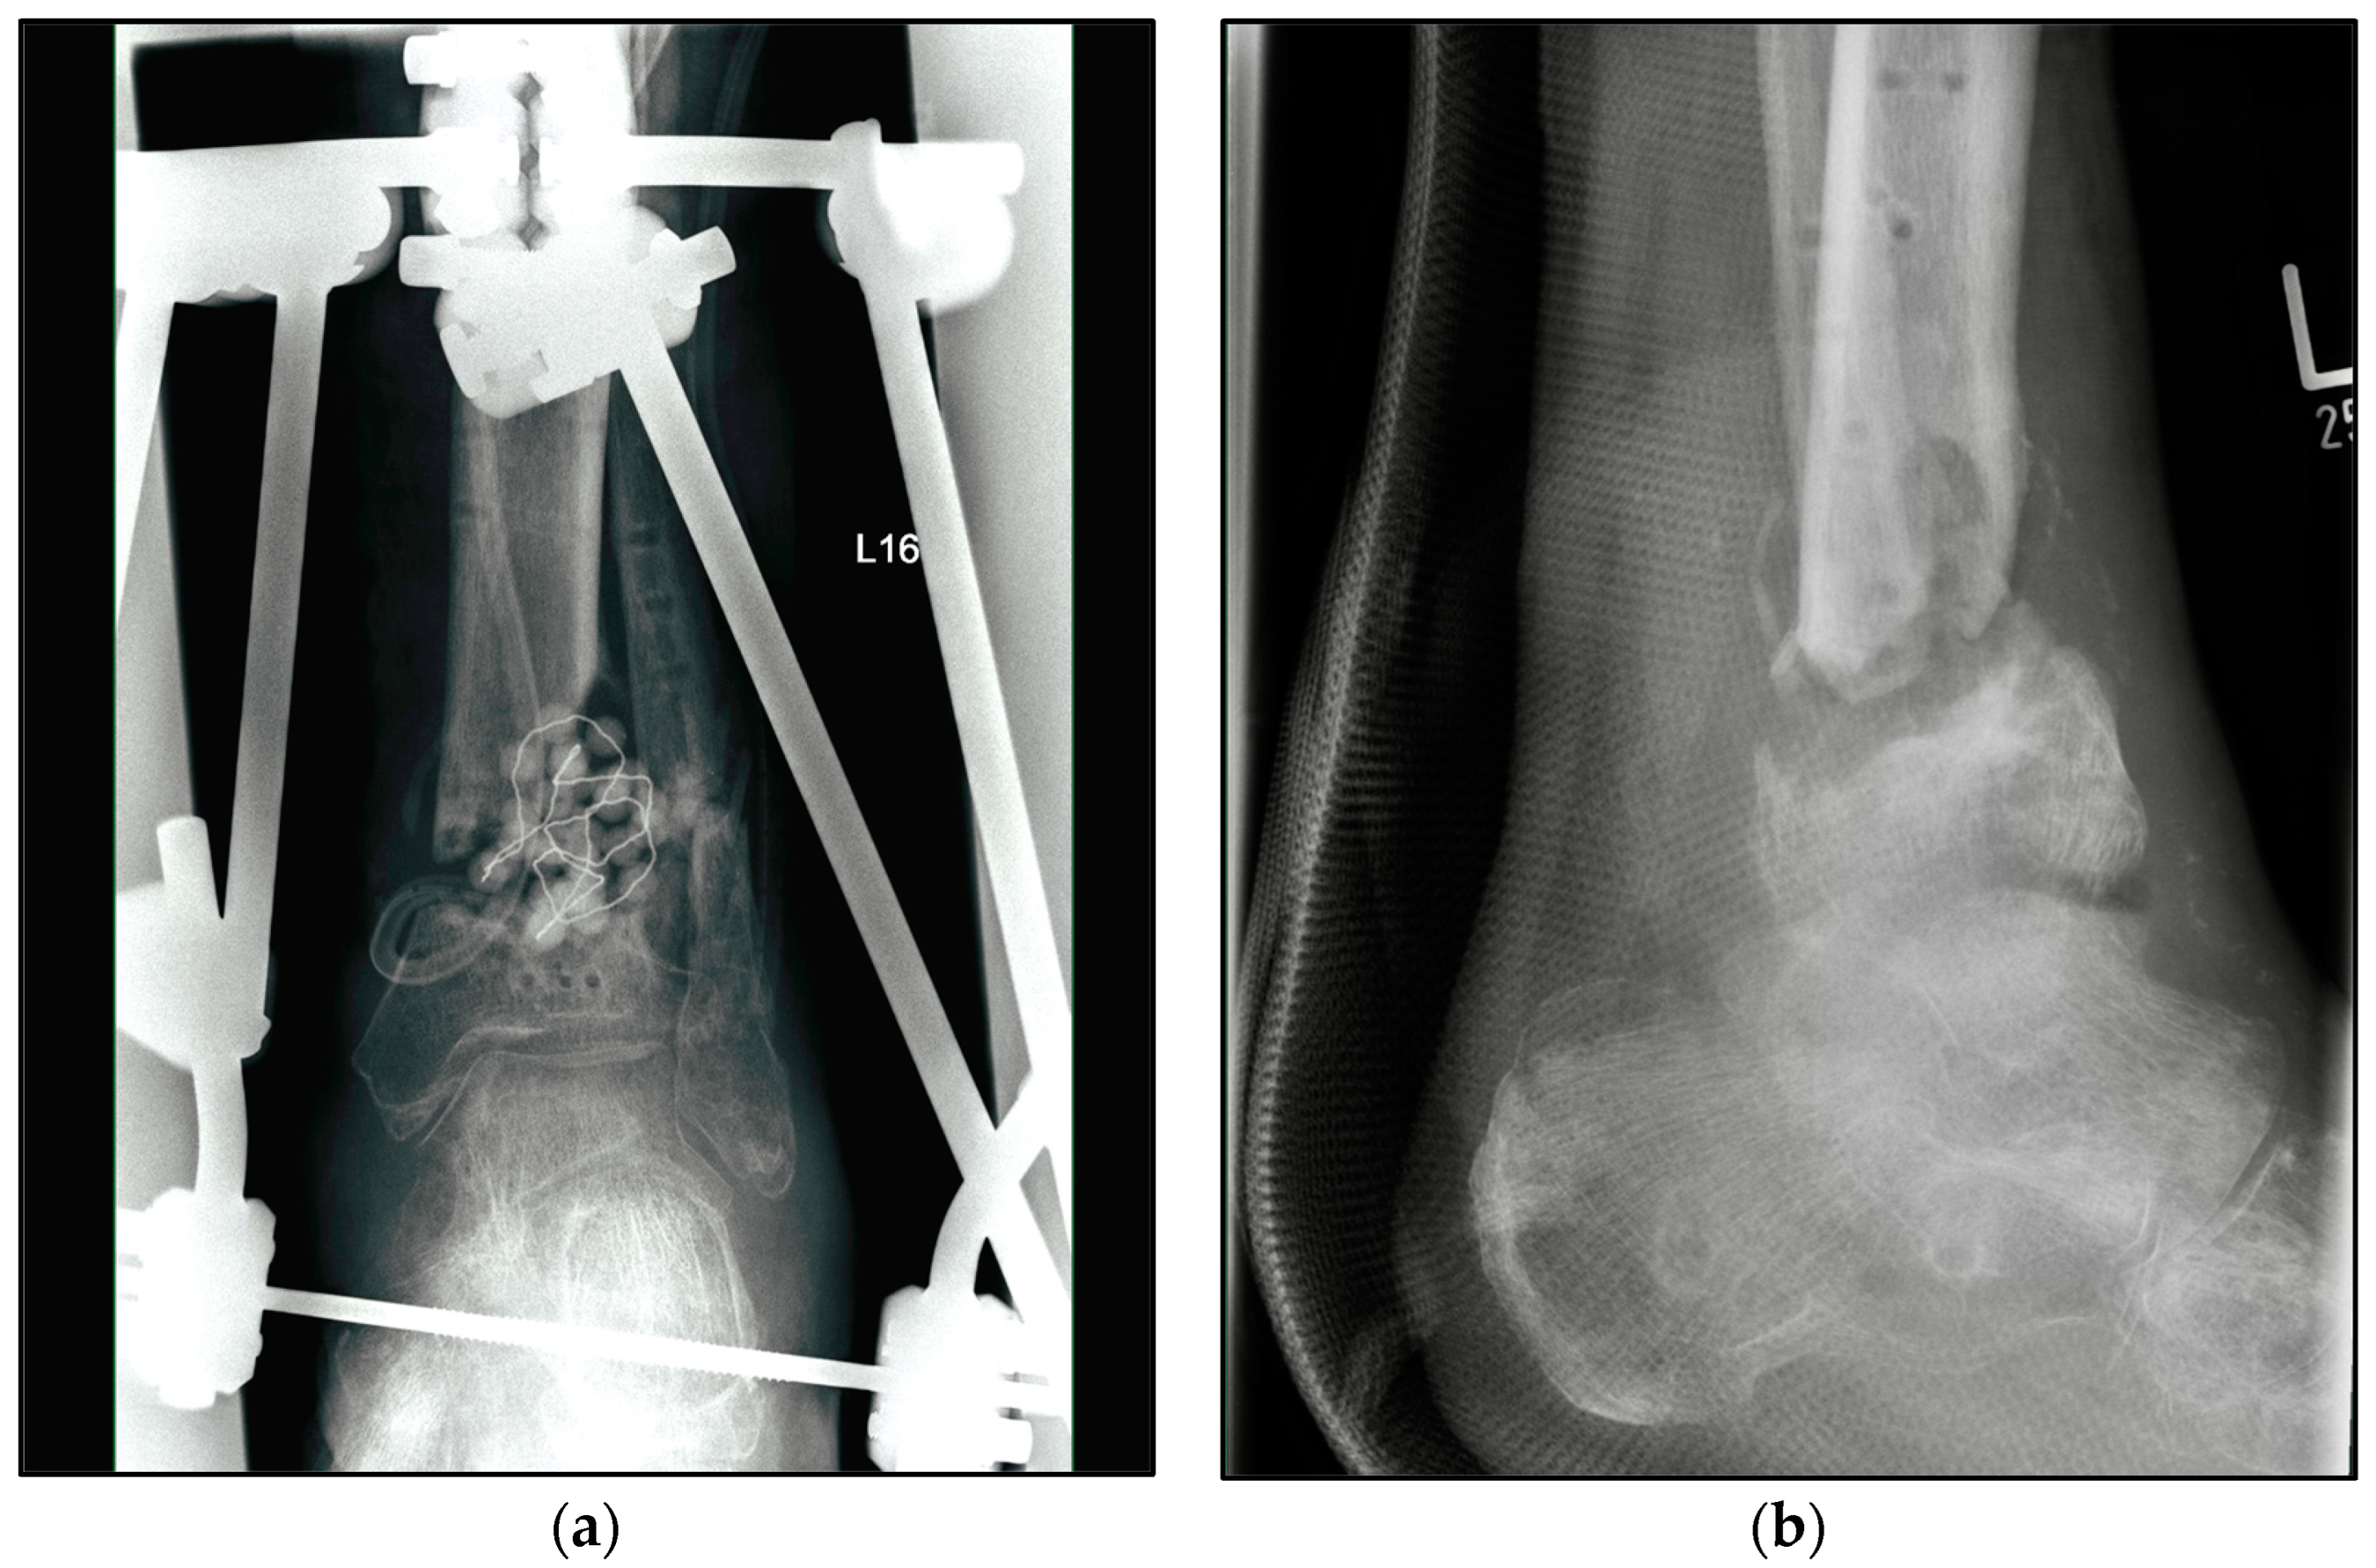

Figure 3.

Radiographic findings of the left ankle of a 82-year-old male patient with condition according to open 3° tibial fracture with septic history and treated with external fixator. (a) Anteroposterior view; (b) lateral view.